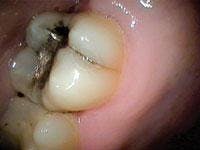

Treatment of the tooth depends on the degree of pulpal involvement and the extent of the crack. Those cracks, which are visualized but remain asymptomatic and clinical testing (such as percussion, palpation, mobility, probing, and thermal testing) is within normal limits, should be treated with a crown or some other form of complete cuspal coverage (see Figure 3). This is to prevent further propagation of the crack and the onset of symptoms. However, if a patient exhibits more extensive symptoms from the start, including increased sensitivity to thermal provocation and percussion/biting, root canal therapy should be performed prior to placement of a crown. These are considered incomplete vertical root fractures. A study by Kahler8 showed that all symptomatic cracks in teeth appeared to extend right through the dentin to the dentino-enamel junction and were extensively contaminated by bacteria. Hence, root canal therapy and crowning for all symptomatic cracks are recommended.

Upon initiation of root canal therapy, the tooth should be examined under a microscope to further evaluate the extent of the crack. Teeth that are considered restorable are those where the crack is confined to the crown portion of the tooth, coronal to the mucogingival complex. Cracks that extend across the furcation of the tooth, or those extending below the osseous crest, and/or are associated with a corresponding narrow deep pocket are complete vertical root fractures and have a poor prognosis. Teeth with complete vertical root fractures are considered nonrestorable and should be extracted (see Figure 2).9,10